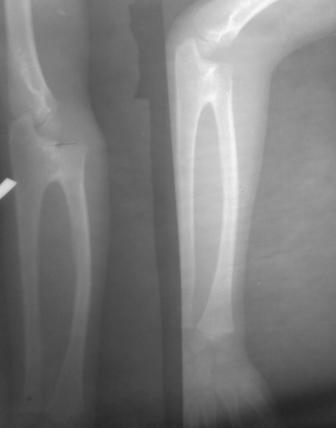

Уважаемые коллеги. Обратился мальчик 10 лет, с врожденным синостозом в проксимальном эпиметафизе лучевой и локтевой кости,

Уважаемый Абдурашид. Не совсем обычная рентгенологическая картина для врожденного синостоза проксимального радиоульнарного сочленения. Отсутствие (рентгенологически) выраженной дугообразной деформации диафиза лучевой кости заставляет думать о минимальной выраженности пронационной контрактуры предплечья.